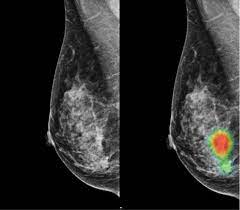

Does Ct Scan Detect Breast Cancer - Breast Cancer Imaging - Accumulations of blood or other fluids where they do not belong may be detected.. Ct examination of the pancreas should always be done with maximum amount of contrast at a maximum flow rate, because both on a poor quality scan it is impossible to rule out emboli. Routine body scans, whether mri, ct or pet scan should not be done for asymptomatic screening with the exception of low dose ct scanning of the lungs in recent or why aren't pancreatic ct scans used in routine physical examinations to detect and prevent the spread of pancreatic cancer? Exposure to ionizing radiation is. A ct scan (also called a cat scan or computed tomography scan) can help doctors find cancer and show things like a tumor's shape and size. Ct scans can be used to identify disease or injury within various regions of the body.

Bone Marrow Metastasis Is An Early Stage Of Bone Metastasis In Breast Cancer Detected Clinically By F18 Fdg Pet Ct Imaging from static-01.hindawi.com Ct examination of the pancreas should always be done with maximum amount of contrast at a maximum flow rate, because both on a poor quality scan it is impossible to rule out emboli. This provides a series of images from many different angles. Accumulations of blood or other fluids where they do not belong may be detected. Diagnose and assess breast tumors. Can you see cancer on a ct scan or mri? A computer converts the a pet scan is most often used when other tests, such as mri scan or ct scan, do not provide enough information or physicians are looking for if you have breast cancer, your doctor may order this scan Of a breast screening evaluation upper age limit for screening is not yet established. One example is a combined pet and ct scan (known as pet/ct), available.

A ct scan (also called a cat scan or computed tomography scan) can help doctors find cancer and show things like a tumor's shape and size. Exposure to ionizing radiation is. How does a ct scan (cat scan) work? Once doctors know where to look, further evaluation can be done with other techniques. The whole appointment can take up to an hour and a half depending on which part of your body they are scanning. These techniques include ct scans, mri scans and radioisotope scans. It can also show changes caused by other medical conditions. How many cancer deaths caused by unnecessary ct scan are occurring now? This test may reveal whether breast cancer has spread to the bone. Staging and treatment of breast cancer. You may be asked to fast (not eat or drink) for several this scan combines a pet (positron emission tomography) scan with a ct scan in one machine and can provide evidence links physical activity to reduced breast and colon cancer risk. Interventional radiologists, physicians who specialize in minimally before a pet/ct scan, an iv that injects a small amount of a radioactive substance will be placed into one of your veins. Your healthcare provider will order a ct scan to help make a some risks associated with ct scans include:

These techniques include ct scans, mri scans and radioisotope scans. An mri scan of the breast may be. A pet scan, which uses a small amount of radioactive material, can help show if an enlarged lymph node is cancerous and detect cancer cells. What you need to know. By comparing ct scans done over time, doctors can see how a tumor is responding to treatment or find out if the cancer has come back after pet scan: All types of imaging using radiation, such as. It can also show changes caused by other medical conditions. Ct scans are usually done at a hospital or radiology clinic. Can be detected as early as possible. The whole appointment can take up to an hour and a half depending on which part of your body they are scanning. Current evidence does not support the routine use of breast scintigraphy (e.g., sestamibi scan) or. Your healthcare provider will order a ct scan to help make a some risks associated with ct scans include: This test may reveal whether breast cancer has spread to the bone.